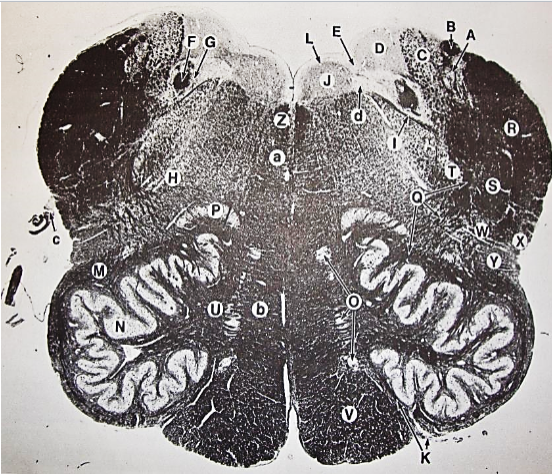

A

Lateral Cuneate nucleus

B

dorsal external arcuate fibers

C + D collectively

vestibular nuclei

C + D collectively

vestibular nuclei

E

dorsal motor nucleus of vagus nerve

F

solitary fasciculus

G

solitary nucleus

H

nucleus ambiguous

I

fascicles of glossopharyngeal nerve

J

hypoglossal nucleus

K

fascicles of hypoglossal nerve

L

dorsal longitudinal fasciculus

M

central tegmental tract

N

inferior olivary nucleus

R

inferior cerebellar peduncle

S

spinal trigeminal tract

T

spinal trigeminal nucleus

U

ventral trigeminothalamic tract

V

pyramidal (corticospinal) tract

W

rubrospinal tract

X

anterior spinocerebellar tract

Y

spinal lemniscus

Z

medial longitudinal fasciculus

a

tectospinal tract

b

medial lemniscus

c

vagus nerve

d

inferior salivatory nucleus

A + B collectively

vestibular nuclear complex

D

solitary fasciculus

E

solitary nucleus

F

nucleus ambiguous

G

fascicles of glossopharyngeal nerve

H

spinal trigeminal tract

I

spinal trigeminal nucleus

J

ventral trigeminothalamic tract

K

central tegmental tract

L

interior olivary nucleus

O

inferior cerebellar peduncle